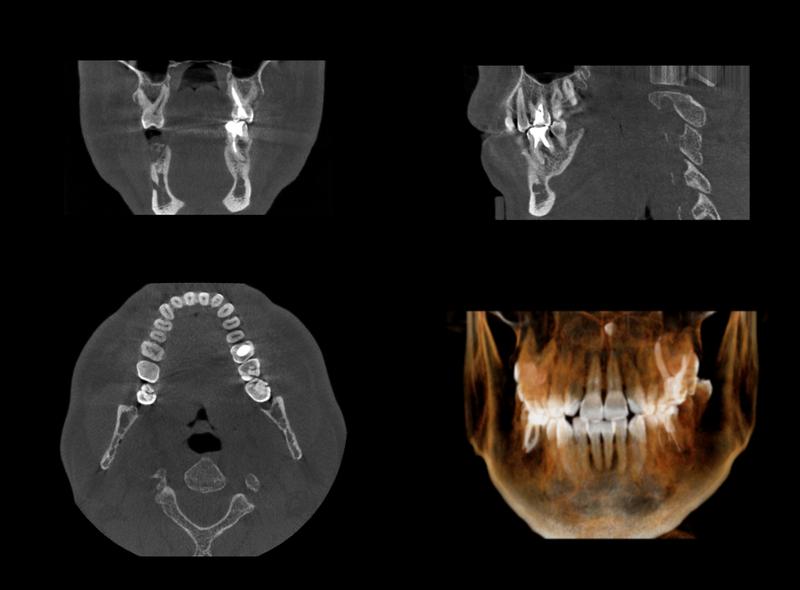

従来の2次元的なレントゲン写真では、複雑な形をした⻭の根の裏側に隠れた病変や、根の破折(割れ)を⾒つけることが困難でした。

当院が採⽤している⻭科⽤CTは、お⼝の中を3次元的な⽴体映像で映し出します。

根の形状、神経の⾛り⽅、そして顎の⾻の中にできている「膿の袋」の⼤きさや位置まで正確に把握できるため、より確実で無駄のない治療計画を⽴てることができます。